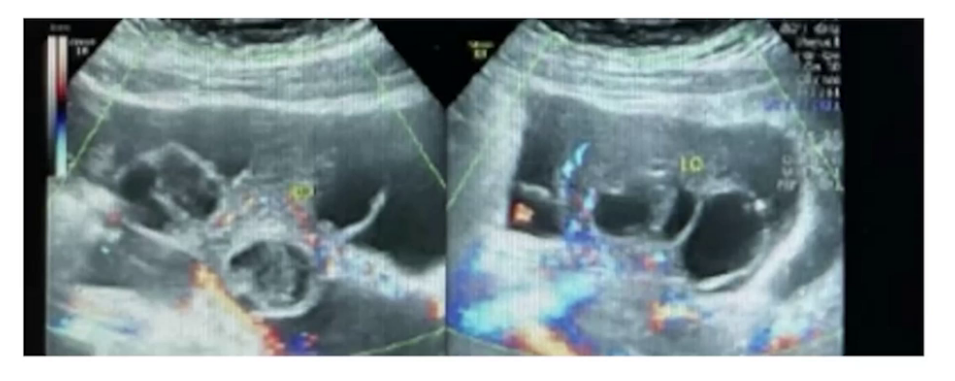

妇科B超检查显示左侧卵巢大小69mm×55mm,右侧卵巢大小87mm×72mm,子宫前方见50mm×43mm液性暗区,子宫后方见78mm×42mm液性暗区。同时检查电解质、肝肾功、凝血功能、血常规,提示低钠低氯,ALT轻度升高,APTT缩短,纤维蛋白原升高,D-二聚体升高,白细胞轻度升高,血小板计数升高。胸水B超检查发现右侧肩胛线第7-8肋间1.2cm无回声区,考虑右侧胸腔少量积液,左侧胸腔未见明显积液。

移植后19天,患者腹胀、胸闷症状明显减轻,出入量平衡,腹围、体重无明显增加,要求出院。移植后3周,B超显示宫内早早孕,两个孕囊,未见胎芽及胎心,继续保胎治疗。移植后4周,B超显示宫内早孕双胎存活。